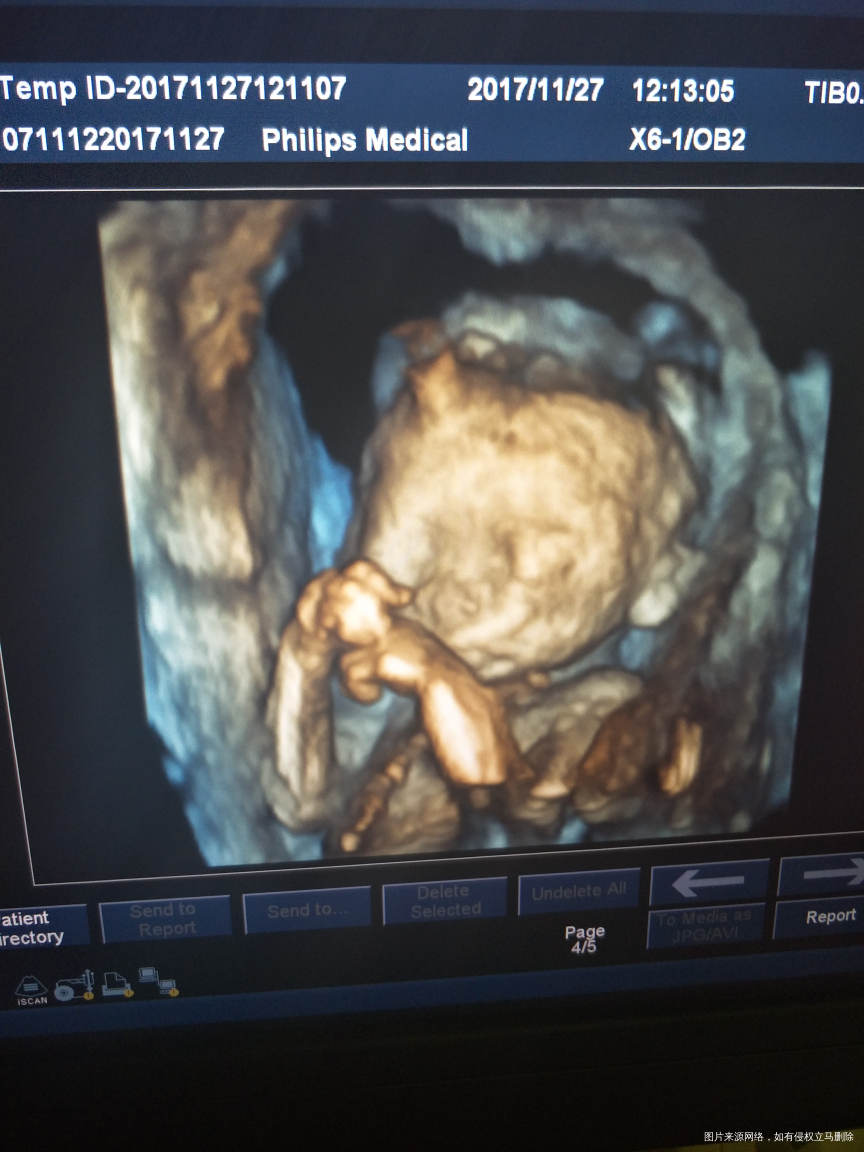

做的四维彩超,医生说有点偏小,不知道是不是严重偏小了,医生说没有明显畸形,其他的也没有仔细问医生,麻烦各位医生看看宝宝有没有严重偏小,有没有脐带绕颈。

目前孕周22周加1但B超显示宝宝只有四个多月

确实小的挺多,早孕期的检查和停经时间相符吗?

末次是6月27号,8月份检查的时候是还好,12周检查是小了两周,后面去复查又长了上来了,医生说是我不爱吃的原因

末次6月27号,八月份检查的时候是还好,到了12周后找检查是小了一个星期零几天,输了两天液,后面15周去复查是长上来了,前天去做四维医生说营养都被我吸收掉了

增加营养,半个月后复查